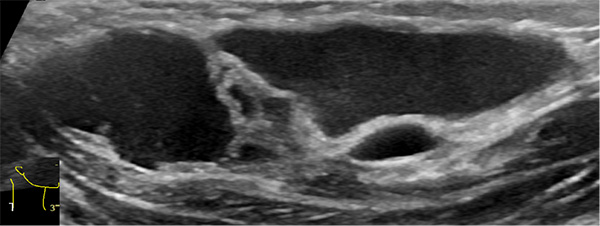

超声难以确诊的病例,或病变周围结构较复杂(如在颈部、纵隔等部位)以及位置较深(如在腹腔、盆腔等部位)治疗难度大、风险高时,往往需加做磁共振检查,更精确评估病情。当影像学检查难以诊断时,也可行诊断性穿刺,若穿刺抽出淡黄色清亮淋巴液即可诊断为淋巴管畸形,若抽出陈旧性血液结合细胞学检查可诊断为淋巴管瘤伴出血。

淋巴管囊肿磁共振检查